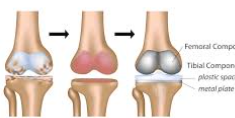

무릎 관절염으로 고생하는 환자들에게 줄기세포 치료는 인공관절 수술을 피할 수 있는 혁신적인 대안으로 주목받고 있습니다. 하지만 치료를 고려할 때 가장 먼저 궁금한 것은 바로 비용입니다. 무릎 줄기세포치료비용은 치료 방법과 병원에 따라 큰 차이를 보이며, 올바른 정보 없이는 과도한 비용을 지불할 위험이 있습니다.

무릎 줄기세포치료는 관절염의 진행 단계에 따라 효과가 달라집니다. 2-3기 중기 관절염에서 가장 효과적이므로, 적절한 시기에 치료받는 것이 비용 대비 효과를 극대화하는 방법입니다.

너무 초기에 치료받으면 보존적 치료로도 충분할 수 있고, 너무 늦으면 인공관절 수술이 더 나은 선택일 수 있습니다. 정형외과 전문의와 충분한 상담을 통해 최적의 치료 시기를 결정하세요.